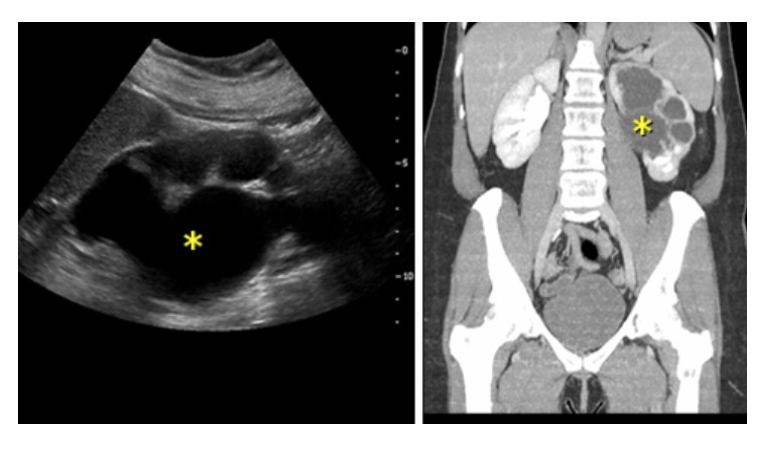

What is the diagnosis

L sided pyelonephritis